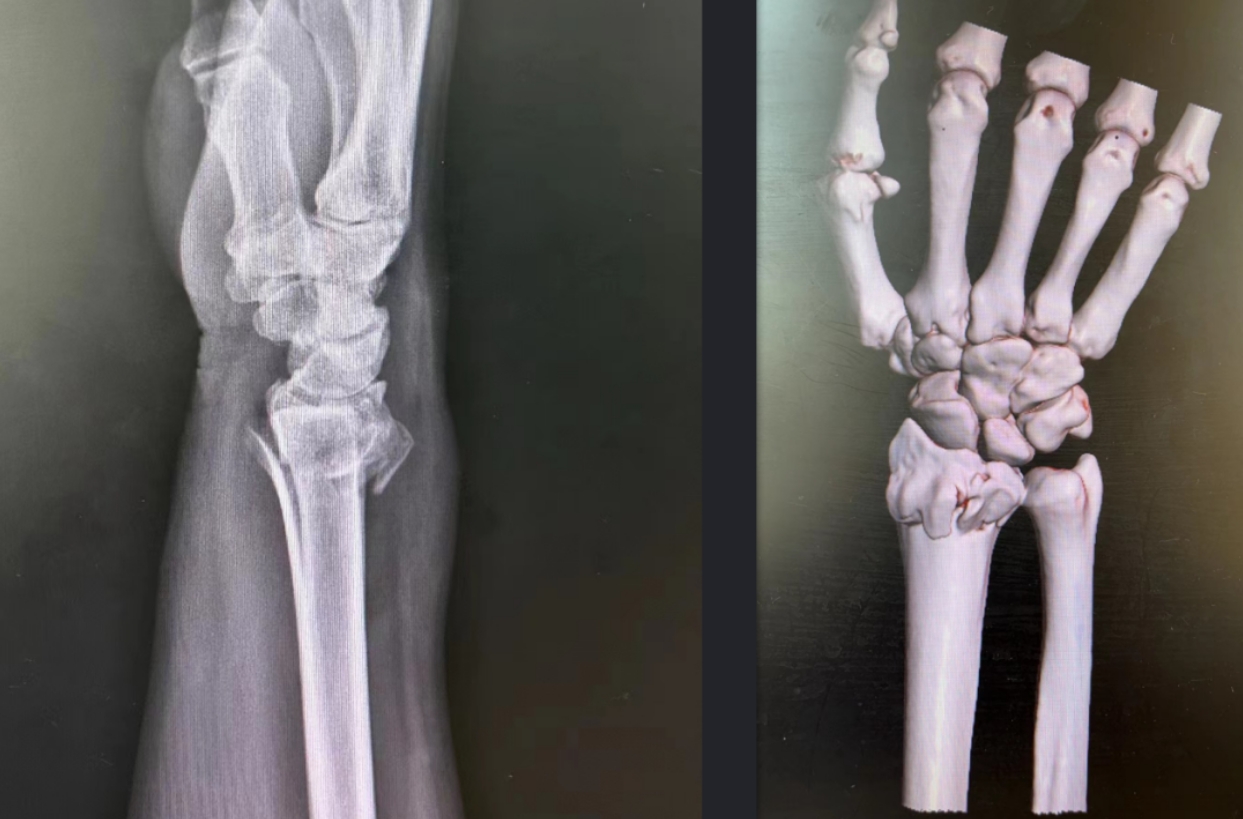

术前实拍

术前影像

术后复查X线片显示,骨折线固定牢固,恢复情况良好。